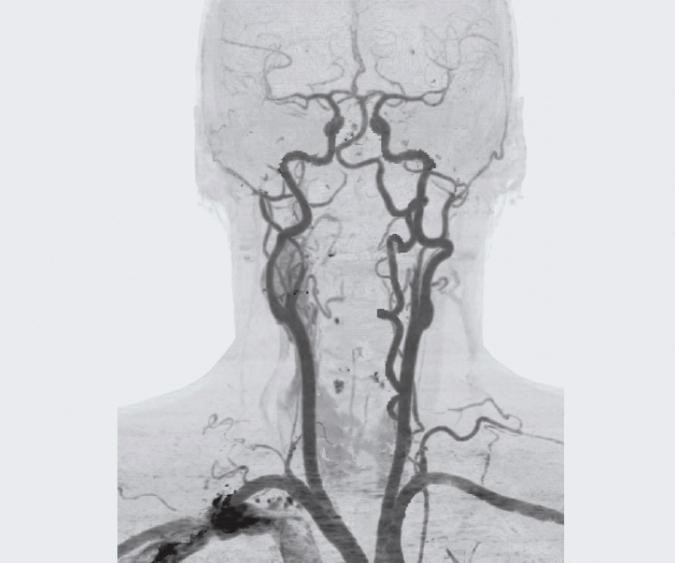

Ангиография брахиоцефальных артерий – это инструментальный метод исследования, позволяющий с помощью рентгеновского излучения увидеть состояние сосудов шеи. Для проведения исследования необходимо введение в соответствующий сосуд контрастного вещества и наличие рентгеновского аппарата, с помощью которого будет зафиксировано изображение сосудов, заполненных этим контрастом. Ангиография брахиоцефальных артерий – это не рутинный метод диагностики, у него имеются свои показания и противопоказания, а также, к сожалению, и осложнения.

Суть этого метода исследования заключается в следующем. Больному в артерии шеи вводится рентгенконтрастное вещество, обычно на основе йода (Оптирей, Омнипак, Ультравист и другие). Это делается для того, чтобы можно было с помощью рентгеновского излучения зафиксировать изображение сосуда, поскольку при обычном снимке сосуды плохо визуализируются. Введение рентгенконтрастного вещества возможно путем пункции соответствующей артерии через катетер, подведенный к необходимому сосуду с периферии (обычно из бедренной артерии). Когда контрастное вещество оказывается в сосудистом русле, производится серия рентгеновских снимков. Полученные снимки оцениваются врачом и делаются выводы о наличии либо отсутствии определенной патологии артерий шеи.